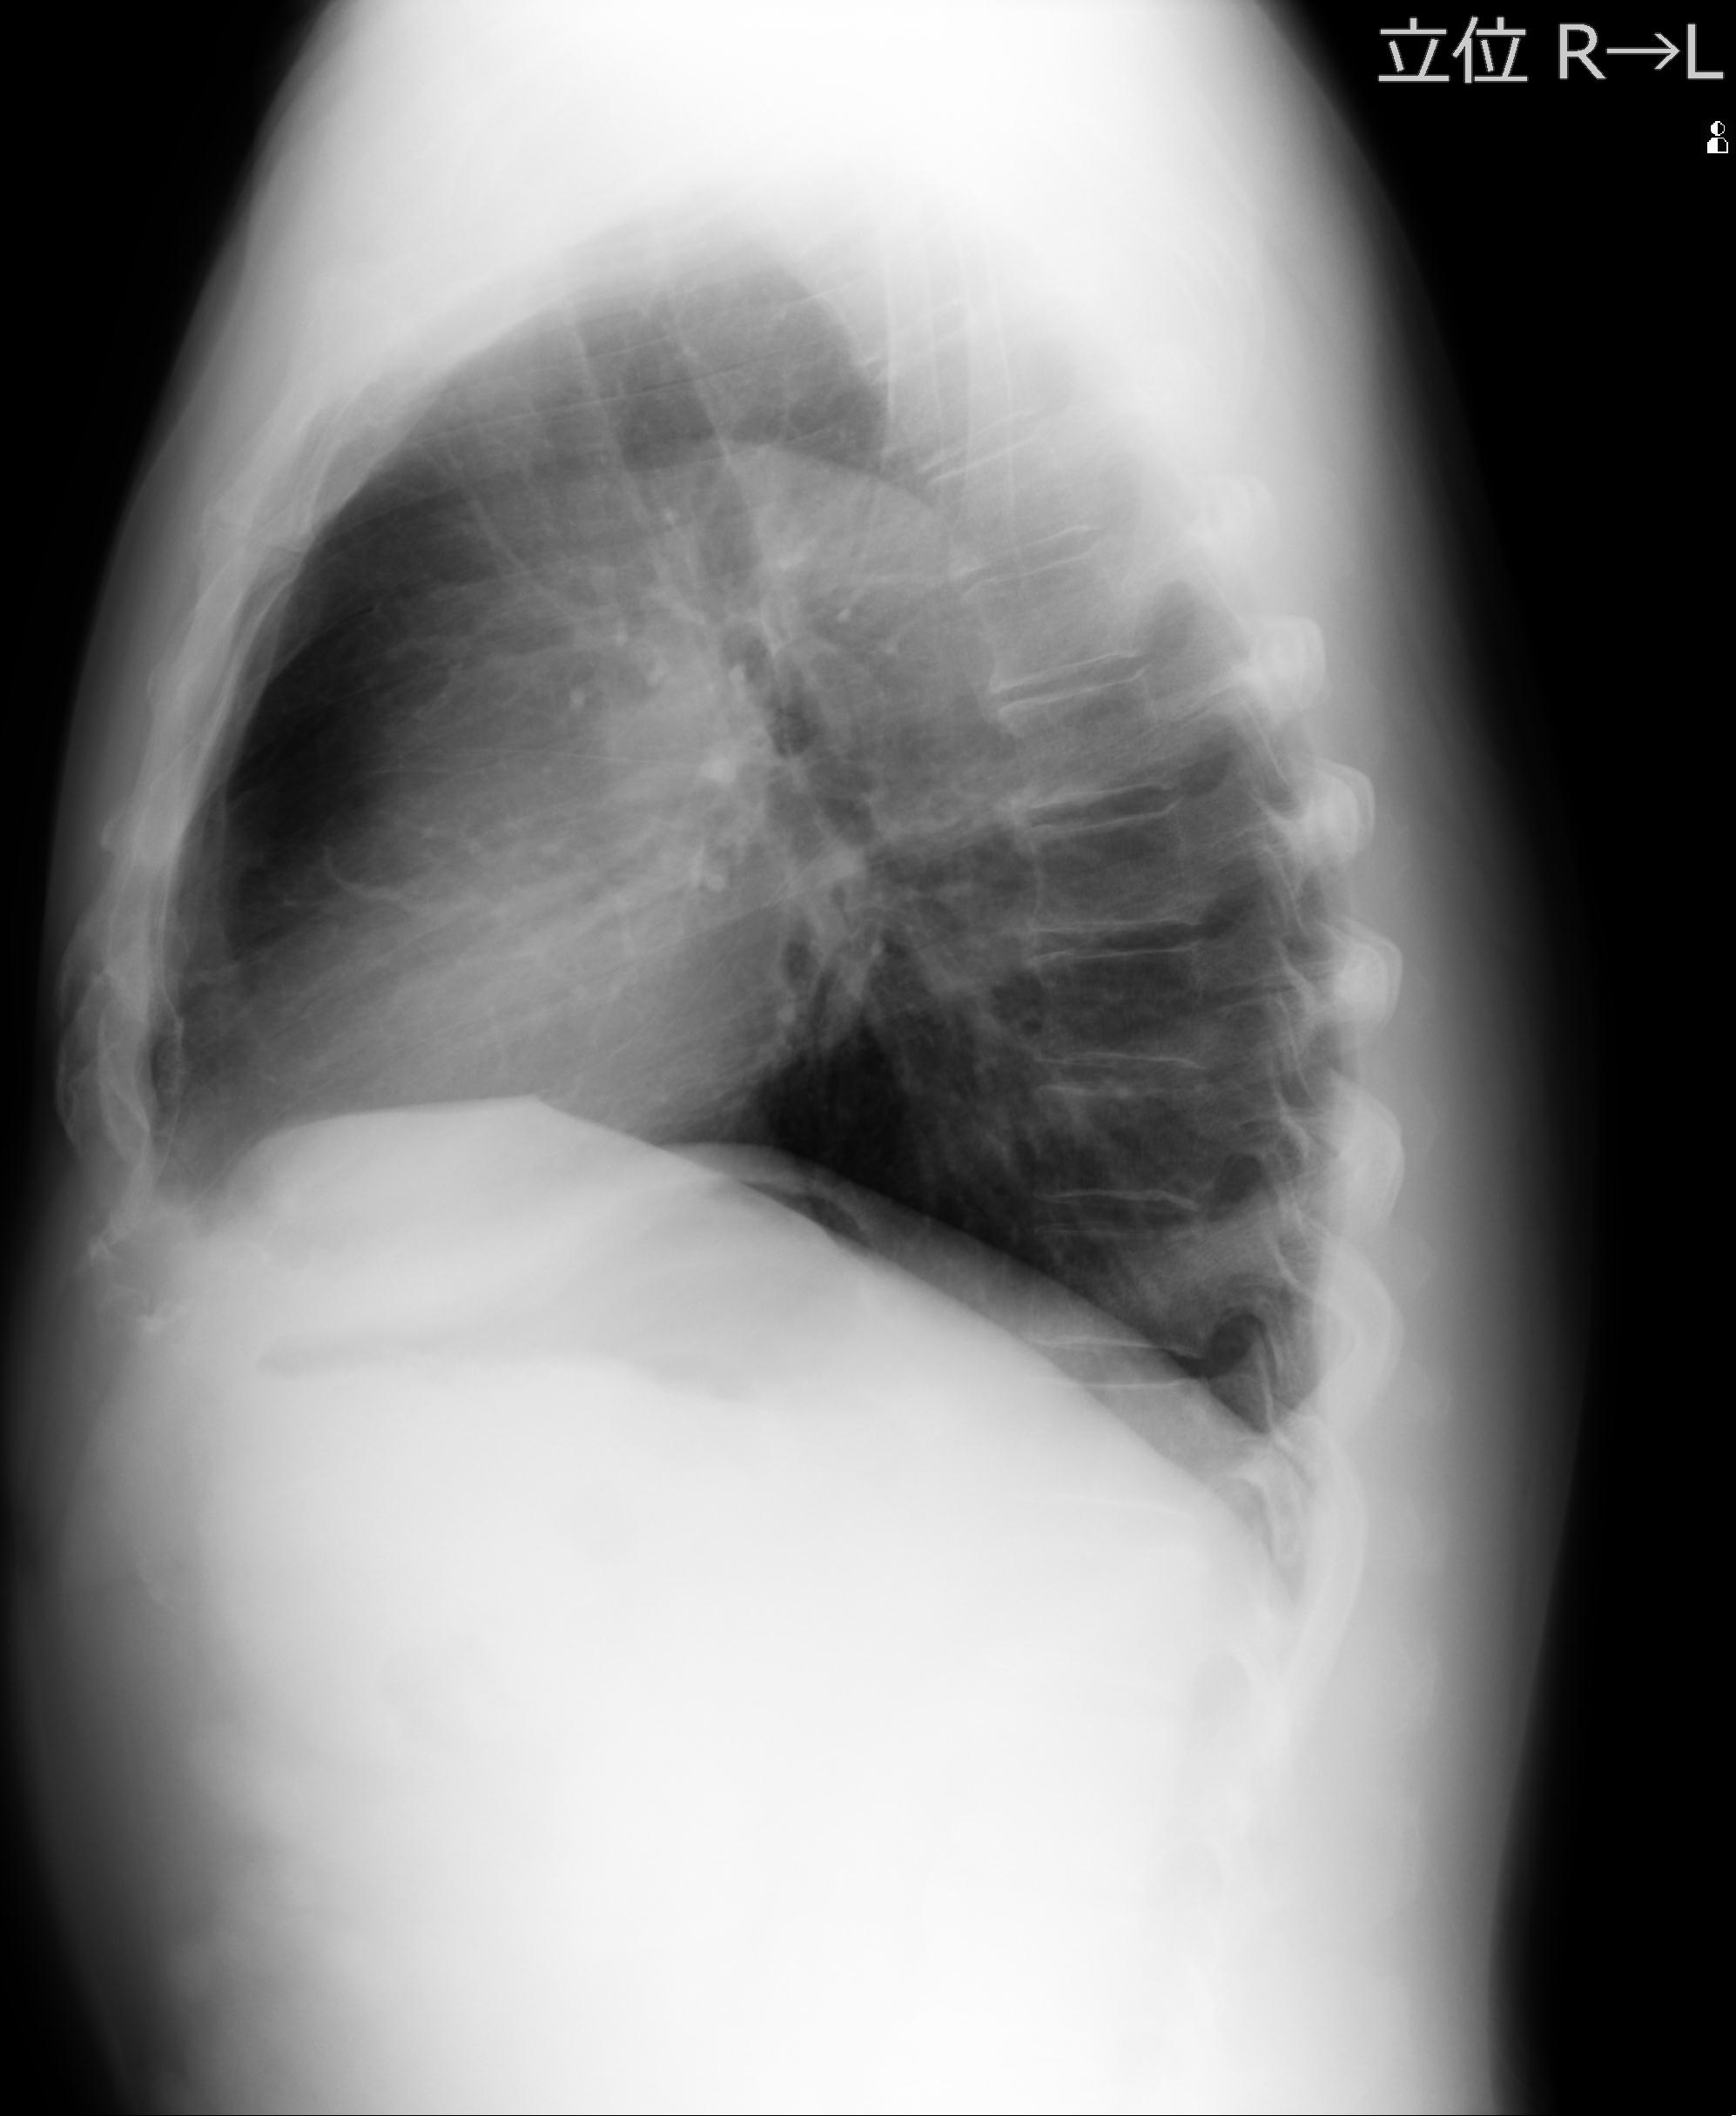

60058 3/9 11/4 右肩 2R+MRI 73歳男性 肩腱板損傷